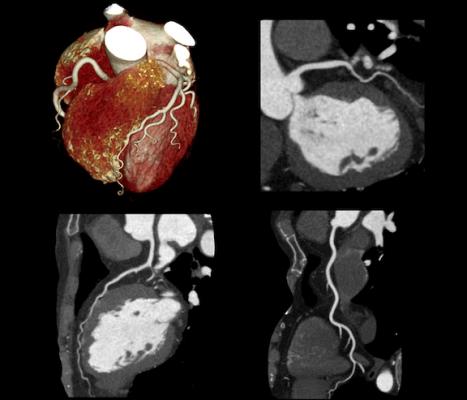

Angiotomografía de Coronarias

Una angiogtomografía coronaria es una prueba de diagnóstico por imágenes para observar las arterias que suministran sangre al corazón. Se podría hacer para diagnosticar la causa del dolor de pecho u otros síntomas.

Una angiotomografía coronaria utiliza una potente máquina de rayos X para producir imágenes del corazón y sus vasos sanguíneos. El procedimiento no es invasivo y no requiere tiempo de recuperación. Las angiotomografías coronarias se utilizan para diagnosticar diversas afecciones cardíacas.

Una angiotomografía coronariaes diferente de una angiografía coronaria estándar. En el procedimiento tradicional (angiografía sin TC), se pasa un tubo flexible (catéter) por la ingle o el brazo hasta el corazón o las arterias coronarias. Si tienes una enfermedad de las arterias coronarias conocida, tu médico podría recomendar el enfoque tradicional porque también puedes recibir tratamiento durante el procedimiento.